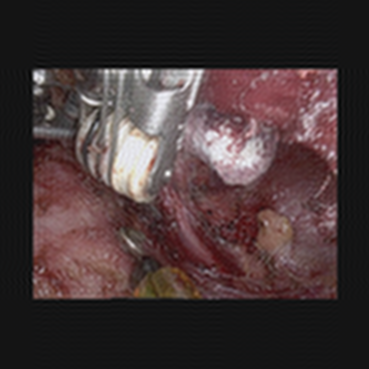

The medical images considered are obtained from a video of a surgery called Bilateral Axillo-Breast Approach (BABA) robotic thyroidectomy, approved by the Research Ethics Committee of Seoul National University Bundang Hospital (B-2504-969-701). This is a thyroid surgery method that is representative of remote access surgery. Clinically, BABA surgery is well known for its superior cosmetic effects and lower complications than conventional thyroidectomy. This surgical method creates surgical incisions in both axillae and both areolas and uses the da Vinci robot to perform the surgery. The surgical video is recorded during the surgery, and the high-resolution images captured are analyzed to develop meaningful clinical studies. Therefore, encoding a high quality of image into a quantum circuit may be significantly important for the future of clinical studies.

We performed similar numerical simulations for more images taken at different frames. Fig. 5 compares the original zero-padded images, the corresponding reconstructed images using FAQPIE with and without the combination of two compression techniques with the same parameter setting as in Fig. 4. A similar observation is made that encoding the images with the two compression techniques results in more efficient FAQPIE with reasonable surgical details and lowered gate counts, as summarized Table 3.

Refer to caption

Figure 5: Comparison of original medical images (left), the corresponding reconstructed images via FAQPIE with no compression technique (middle) and the two compression techniques applied as in Fig. 4 (right).